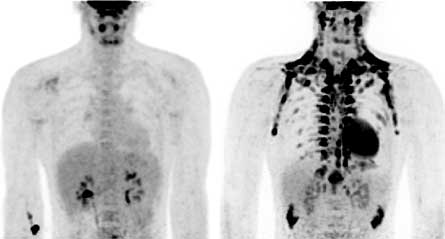

In the first study, researcher Ronald Kahn of the Joslin Diabetes Center and Harvard Medical School in Boston looked at the medical records of nearly 2,000 people who had received a PET-CT scan. To get a PET, or positron emission tomography, scan, a person is injected with a chemical that emits particles called positrons. Inside the person’s body, these positrons create radiation called gamma rays, which pass through the body and are detected by special machines outside the body. This type of scan provides a three-dimensional picture of what’s going on inside the body. PET scans are often used to diagnose cancer. A CT scan uses X-rays to see inside a body.

The connection between brown fat and temperature was explored in the second study. Dutch researchers took scans of lean and overweight men at two temperatures, 72 degrees Fahrenheit (room temperature) and 61 degrees Fahrenheit. At the higher temperature, brown fat barely appeared on the scans. But when the temperature dropped, brown fat appeared on the scans of the leaner men. The more overweight the man, the less brown fat appeared. The third study, conducted by Swedish scientists, also found evidence of brown fat in adults.